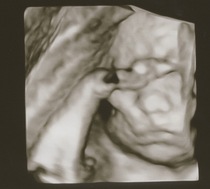

After lots of back and forth, we decided to splurge on a 3D/4D ultrasound as my hospital was offering it for a reasonable price and I felt it would be safe doing it there (felt nervous about a private clinic with this technology for some reason, even though I went to one previously for normal ultrasound).

The experience was equal parts weird and amazing! It was like looking around underwater or on another planet (my uterus) - but seeing the baby move normally, suck his thumbs and rub his eyes was just incredible and reassuring. Some of the pictures came out pretty creepy due to black spots for eyes etc, but a few were cute and we got to see his little face clearly despite my anterior placenta (which baby was cuddling with).

Also, they told us he's measuring 2.5 lbs (1.16 kg) and is in the 73 growth percentile for 27w2d, I hope that doesn't bode poorly for my GD glucose test next week...

@WolfMother326 I wake at different times in the night at least twice, I have to go to the loo every time I wake now and was woken with some big kicks last night. I woke on my back and they kicked me so hard so they were probs saying mum shift it 😂🤣 lovely pics !

@WolfMother326 aw look at those photos! He looks like a cutie already! Your pictures look super clear compared some others I’ve seen. Fingers crossed all clear got GD, 73 just sounds good sized to me 😊